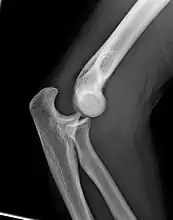

The elbow undergoes dynamic development of ossification centers through infancy and adolescence, with the order of both the appearance and fusion of the apophyseal growth centers being crucial in assessment of the pediatric elbow on radiograph, in order to distinguish a traumatic fracture or apophyseal separation from normal development. The order of appearance can be understood by the mnemonic CRITOE, referring to the capitellum, radial head, internal epicondyle, trochlea, olecranon, and external epicondyle at ages 1, 3, 5, 7, 9 and 11 years. These apophyseal centers then fuse during adolescence, with the internal epicondyle and olecranon fusing last. The ages of fusion are more variable than ossification, but normally occur at 13, 15, 17, 13, 16 and 13 years, respectively.[16] In addition, the presence of a joint effusion can be inferenced by the presence of the fat pad sign, a structure that is normally physiologically present, but pathologic when elevated by fluid, and always pathologic when posterior.[17]